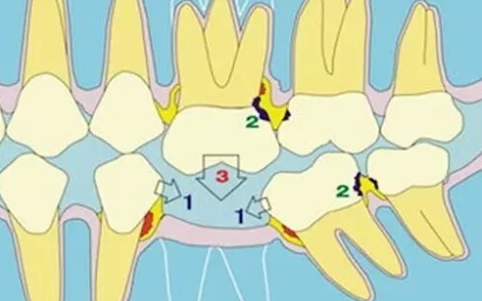

传统方法镶装的假牙,由于没有牙根的支持,全口假牙的基托是骑跨在牙床上,靠口腔唾液的吸附来固位,牙床粘膜直接受力;而部分缺牙镶装的假牙,多靠邻牙的支持,在邻牙上需作卡环固位或切割邻牙作牙套固位,邻牙易受损伤。种植牙彻底改变了传统假牙的支持和固位方式,使假牙与牙槽骨直接连接在一起。不但大大地提高了假牙的固位力、稳定性、彻底摆脱了传统镶牙对邻牙的损害,而且将咀嚼感觉、功能恢复到接近自然牙的水平。